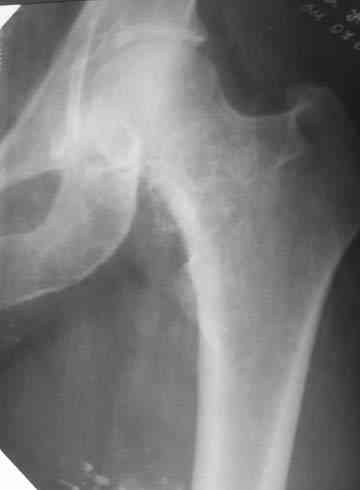

Боль постепенно усиливалась в течении последних 2 лет. Лечилась амбулаторно у невролога по месту жительства с диагнозом остеохондроз поясничного отдела позвоночника, корешковый синдром. В общих и биохимических анализах крови изменений не отмечалось, ревматоидный фактор (РФ), С-реактивный белок – в пределах нормы. Рентгенологическое исследование. В прямой и боковой проекции левого тазjбедренного сустава отмечается уплотнение крыши вертлужной впадины. В мягких тканях определяются округлой формы участки неравномерного обызвествления. Заключение. ДОА тазобедренного сустава. Хондроматоз слева в мягких тканях. Клиника. Видимых деформаций в области тазобедренного сустава нет. Ограничено отведение в левом тазобедренном суставе из-за болей до 20º. На основании клинических и лабораторных показателей был поставлен диагноз "Хондроматоз левого тазобедренного сустава". После стандартного предоперационного обследования выполнена диагностическая артроскопия тазобедренного сустава – обнаружены свободно лежащие внутрисуставные хондральные тела > 2 см в диаметре, хондромаляция хряща головки бедренной кости II степени. Выполнена боковая артротомия, внутрисуставные тела удалены, синовиальная оболочка частично резецирована. Послеоперационное течение – без осложнений. Швы сняты в срок, заживление первичным натяжением. Назначен курс лечебной физкультуры. Учитывая наличие рентгенологических признаков коксартроза, проведен курс внутрисуставной вискосуплиментарной терапии препаратами 1% гиалуроновой кислоты № 2. Осмотр через 1 месяц после оперативного лечения. Жалоб на боль при ходьбе нет, движения в полном объеме. Рекомендовано динамическое наблюдение раз в полгода и контрольная рентгенография через год